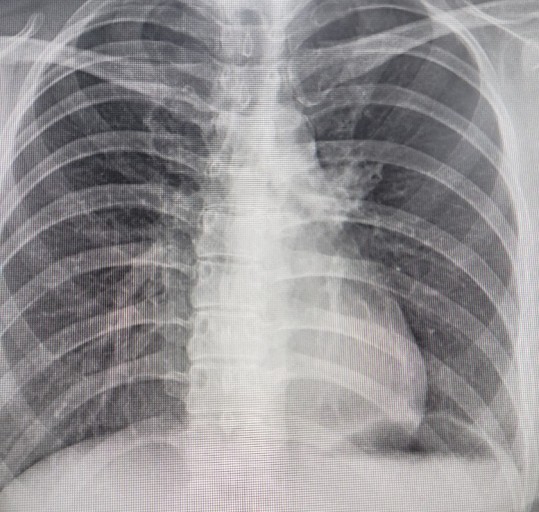

폐렴 증상 폐렴은 폐의 세균, 바이러스, 곰팡이 등 감염으로 인해

폐포(폐 속의 공기 주머니)에 염증이 생기고, 고름이나 액체가 차는 질환입니다.